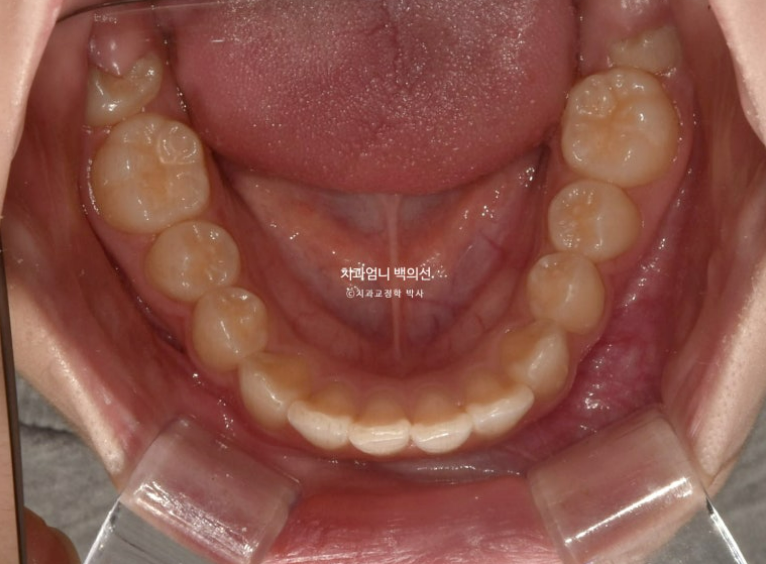

23.09

앞니가 두 개가 아주 커보입니다.

사실 환자분의 앞니가 크진 않습니다. 치아는 입안에서 철저한 원근법을 따르기 때문에 위치적으로 다른 치아에 비하여 앞으로 튀어나와 있으면 상대적으로 커보입니다.

앞니 돌출이 심한편입니다.

돌출이 위에만 국한되어 있어 위에만 작은어금니 2개 발치 후 교정하기로 했습니다.